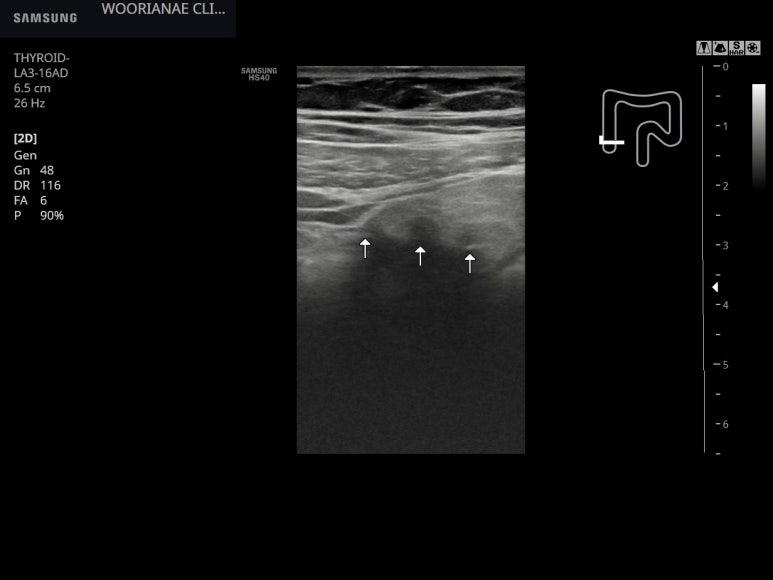

리니어로 보았을 때 맹장 (cecum) 의 전면부로 손가락 처럼 3개의 게실이 보이며

그 중 가장 내측 게실이 주범으로 생각되는 것이 그 주변으로 염증성 지방변화가 둘러싸고 있다.

linear로 전벽에 3개정도의 게실이 관찰됨 (과거와 유사)

; 그 중 가장 내측에 게실 주변으로 염증성 지방변화가 뚜렷, 내측으로 해당 부위가 관찰됨; 최대 압통점과 일치함 linear로 후벽은 관찰되지 않음.